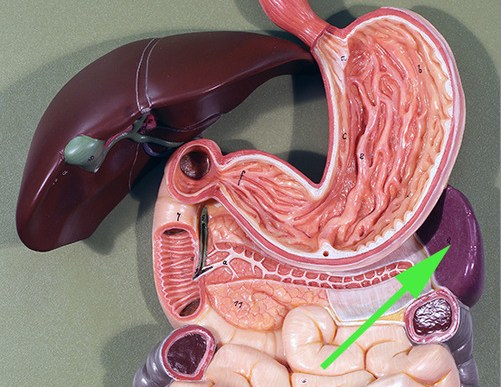

The organ marked by the green arrow arrow is the Spleen

The organ indicated by the green arrow is the SPLEEN